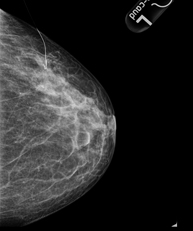

Digital mammography

Digital mammography is an innovative breast examination technique that uses a low radiation dose, thus reducing exposure compared to conventional mammography. The image is digitised using special cassettes on a system known as CR (Computed Radiography). These digitalisation techniques provide excellent images, especially in breasts that are difficult to examine, such as glandular breasts, which appear dense on mammograms, enabling better detection of tumours in this group of patients.

Pre-chemotherapy titanium clipping

Chemotherapy may be administered prior to surgery in the treatment of breast cancer. The tumours decrease in size, sometimes very markedly, making them difficult to locate during surgery. The technique involves placing a titanium clip in the centre of the lesions diagnosed as cancerous. It is performed under ultrasound guidance in most cases, or by mammography.